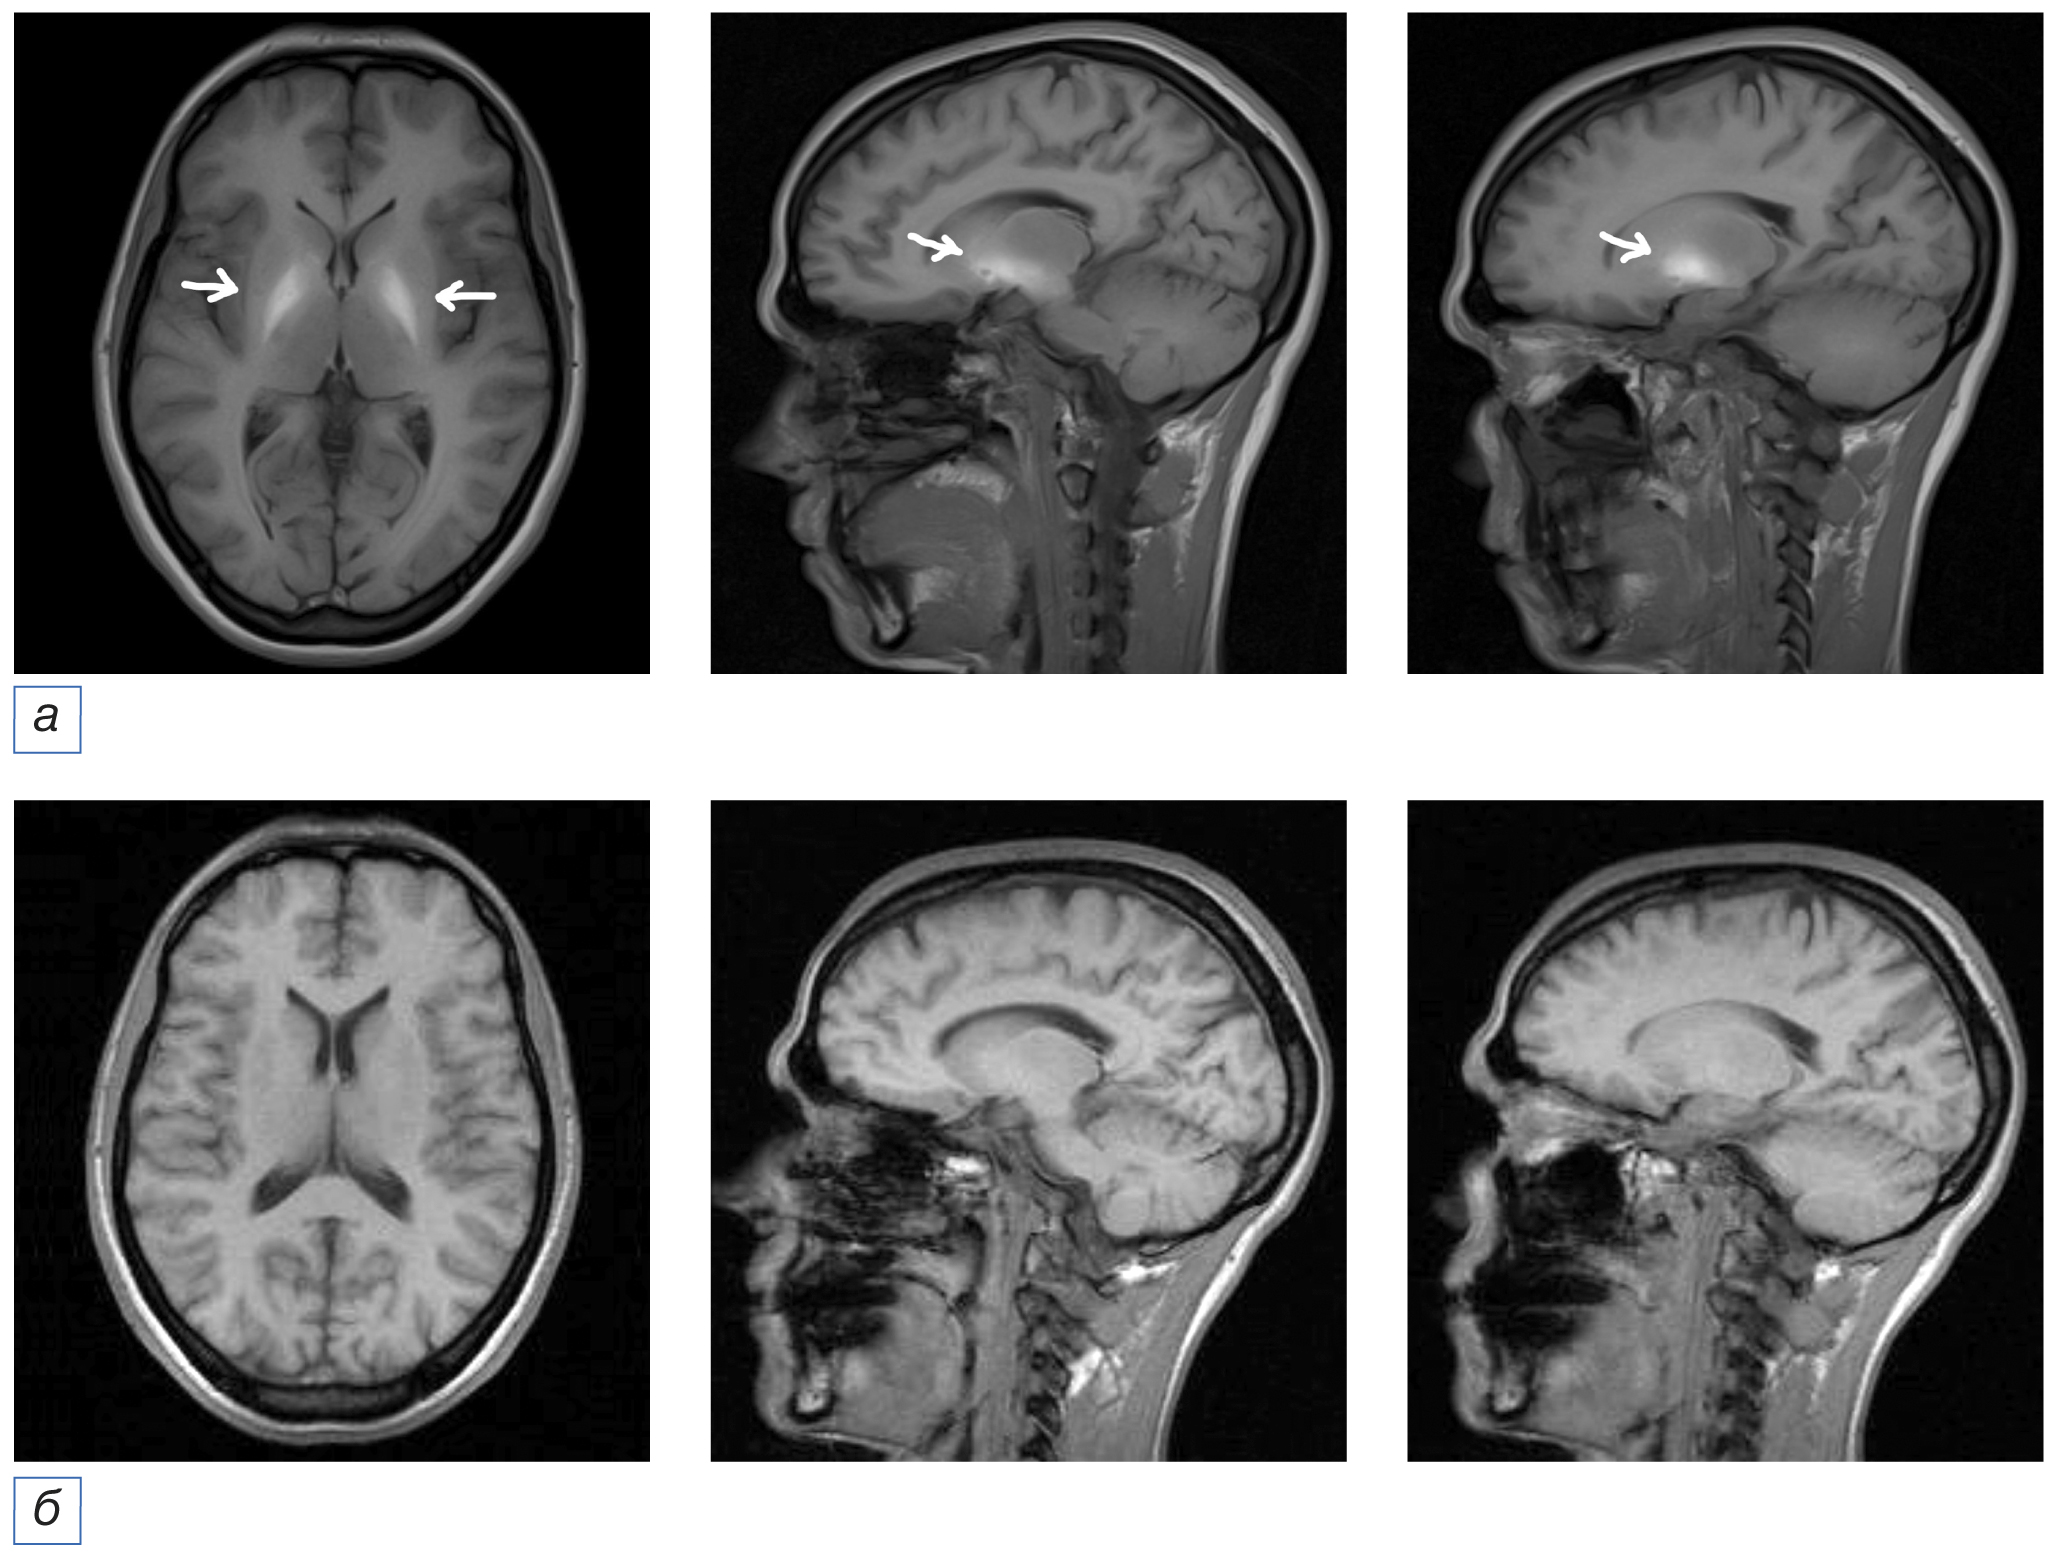

Обращало на себя внимание, что наиболее ранними (в период до 3 лет от дебюта заболевания) в нейровизуализационной картине пациентов с ТДЭ были симметричные очаговые изменения в области базальных ядер, ствола, мозжечка и внутренней капсулы таламуса в виде усиления интенсивности МР-сигнала в режиме Т1-взвешенных изображений (ВИ) и ослабления в режиме Т2-ВИ (7/11 случаев).

Повторное МРТ головного мозга проведено 5 пациентам из 11, прошедших данное исследование в первые 3 года от дебюта заболевания: в динамике отмечался регресс ранее наблюдаемого повышения сигналов от структур мозга (рис. 2).

Рис. 2. Пациентка Б., диагноз токсической дезоморфиновой энцефалопатии. МРТ головного мозга, аксиальная и сагиттальная проекции: а (исследование 2012 г., 32 года, длительность заболевания 1 год) — определяются симметричные зоны повышенного МР-сигнала по Т1-ВИ от базальных ядер (в структурах скорлупы и хвостатых ядер, задних ножках внутренней капсулы, а также по ходу кортикоспинальных трактов, в ножках мозга); б (исследование 2021 г., 41 год, длительность заболевания 10 лет) — в сравнении с предыдущим исследованием ранее выявленные симметричные зоны повышенного МР-сигнала по Т1-ВИ от базальных ядер (в структурах скорлупы и хвостатых ядер, задних ножках внутренней капсулы) не определяются. / Fig. 2. Patient B., diagnosis of toxic desomorphine encephalopathy. Brain MRI, axial and sagittal projections: a (2012 study, 32-year-old, the disease duration was about 1 year) — symmetrical zones of increased MR signal according to TI1-WI from the basal ganglia are determined (in the structures of the putamen and caudate nuclei, the posterior legs of the internal capsule, as well as along the cortico-spinal tracts, in the legs of the brain); б (2021 study, 41 years old, disease duration 10 years) — in comparison with the previous study from 2012, previously identified symmetrical areas of increased MR signal according to T1-WI from the basal ganglia (in the structures of the putamen and caudate nuclei, posterior legs of the internal capsule) are not detected.